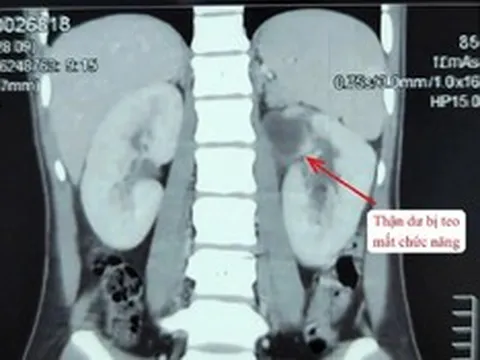

- Gây hại cho thận: Uống thuốc giảm đâu thường xuyên sẽ gây hại cho thận bởi thận là cơ quan bị tác hại nặng nhất nếu lạm dụng thuốc giảm đau. TS Shah nói, vì thuốc giảm đau ức chế sự tổng hợp prostaglandin, việc sử dụng mạn tính có thể dẫn đến suy thận. Từ đó, khiến lưu lượng máu đến thận kém, dị ứng cấp tính với thuốc giảm đau biểu hiện ở thận, khiến protein tràn ra nước tiểu.